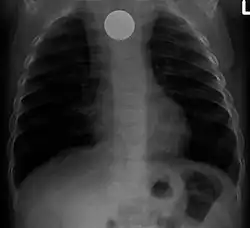

Инородные тела ЖКТ

(слева — в прямой, справа в боковой проекции) — видно инородное тело (монета) пищевода.

Одна из распространённых локализаций инородных тел — желудочно-кишечный тракт. Возможные пути проникновения инородных тел — ротовая полость[13] или прямая кишка[14]. Дети чаще проглатывают монеты[15], у взрослых в 75% случаев инородными телами служили мясные кости[16].

Наиболее часто проглоченные предметы обнаруживают в пищеводе или желудке, реже в глотке или двенадцатиперстной кишке[17].